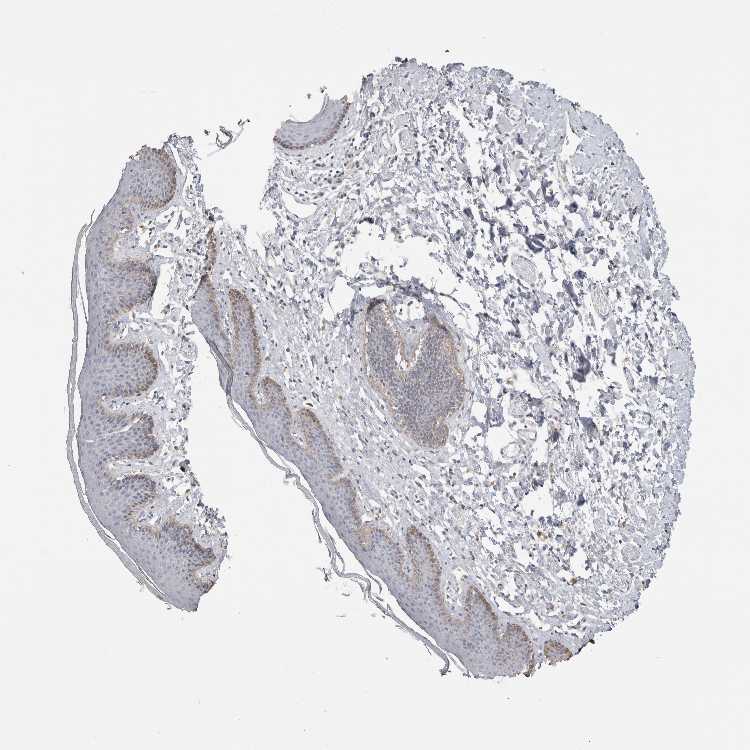

SKIN 1 - Antibody stainingi

Antibody staining in the annotated cell types in the current human tissue is reported as not detected, low, medium, or high, based on conventional immunohistochemistry profiling in selected tissues. This score is based on the combination of the staining intensity and fraction of stained cells.

Each image is clickable and will lead to virtual microscopy that enables deeper exploration of all samples and also displays staining intensity scores, fraction scores and subcellular localization as well as patient and tissue information for each sample.

Antibody HPA024517

Langerhans Low

Fibroblasts Not detected

Keratinocytes Low

Melanocytes Low

SKIN 2 - Antibody stainingi

Epidermal cells Low